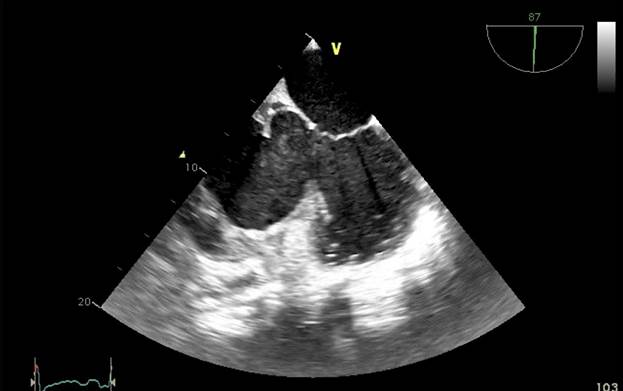

Aproximadamente 3 Semanas posterior al alta presenta cuadro de insuficiencia respiratoria asociado a insuficiencia cardiaca descompensada por lo que acude a nuestro Hospital de Especialidades Abel Gilbert Pontón siendo internada en Unidad Coronaria, a su ingreso se evidencia dolor precordial y torácico bilateral que irradia a región dorsal acompañado de disnea clase funcional NYHA IV/IV, tos persistente y edema leve de miembros inferiores, los laboratorios realizados evidencian anemia leve con hb 10.8 g/dL, péptido natriurético elevado de 12895 pg/ml, enzimas cardiacas negativas, hematuria y proteinuria en uroanálisis; en la radiografía de tórax se muestra cardiomegalia y derrame pleural bilateral; En electrocardiograma taquicardia sinusal, dextrorrotación, complejo QS en cara inferior, sin alteraciones de la onda T y segmento ST. En eco de pleura muestra derrame pleural derecho de moderada a gran cuantía y derrame pleural izquierdo moderado, sospechando de colagenopatía vs enfermedad autoinmune a descartar. Se realiza ecocardiograma transtorácico se evidencia formación aneurismática del VI de 9.5cm x 9.7cm tapizado por trombos con pérdida de la continuidad a nivel perimembranoso septal, además de una miocardiopatía dilatada con FEVI (fracción de eyección del ventrículo izquierdo) 28%. El estudio de líquido pericárdico da como resultado exudado con relación líquido/sérica de LDH 1,8 y proteína 0,7. En ecocardiograma transesofágico (Ilustración 1,2,3) se confirma pseudoaneurisma de gran tamaño del VI en región basal posterior con flujo bidireccional de 10 cm x 7,22cm tapizado de formación trombótica con pérdida de la continuidad de la región basal y posterior del VI con hipocinesia global e hipertensión pulmonar leve con insuficiencia mitral y tricuspidea leve por lo que se decide resolución quirúrgica.

Ilustración 2 Ecocardiograma Transesofágico. Pseudoaneurisma del VI en su porción septal

Fuente: Hospital de Especialidades Guayaquil “Doctor Abel Gilbert Pontón”.

Autor: Dra. María Sánchez Sánchez.